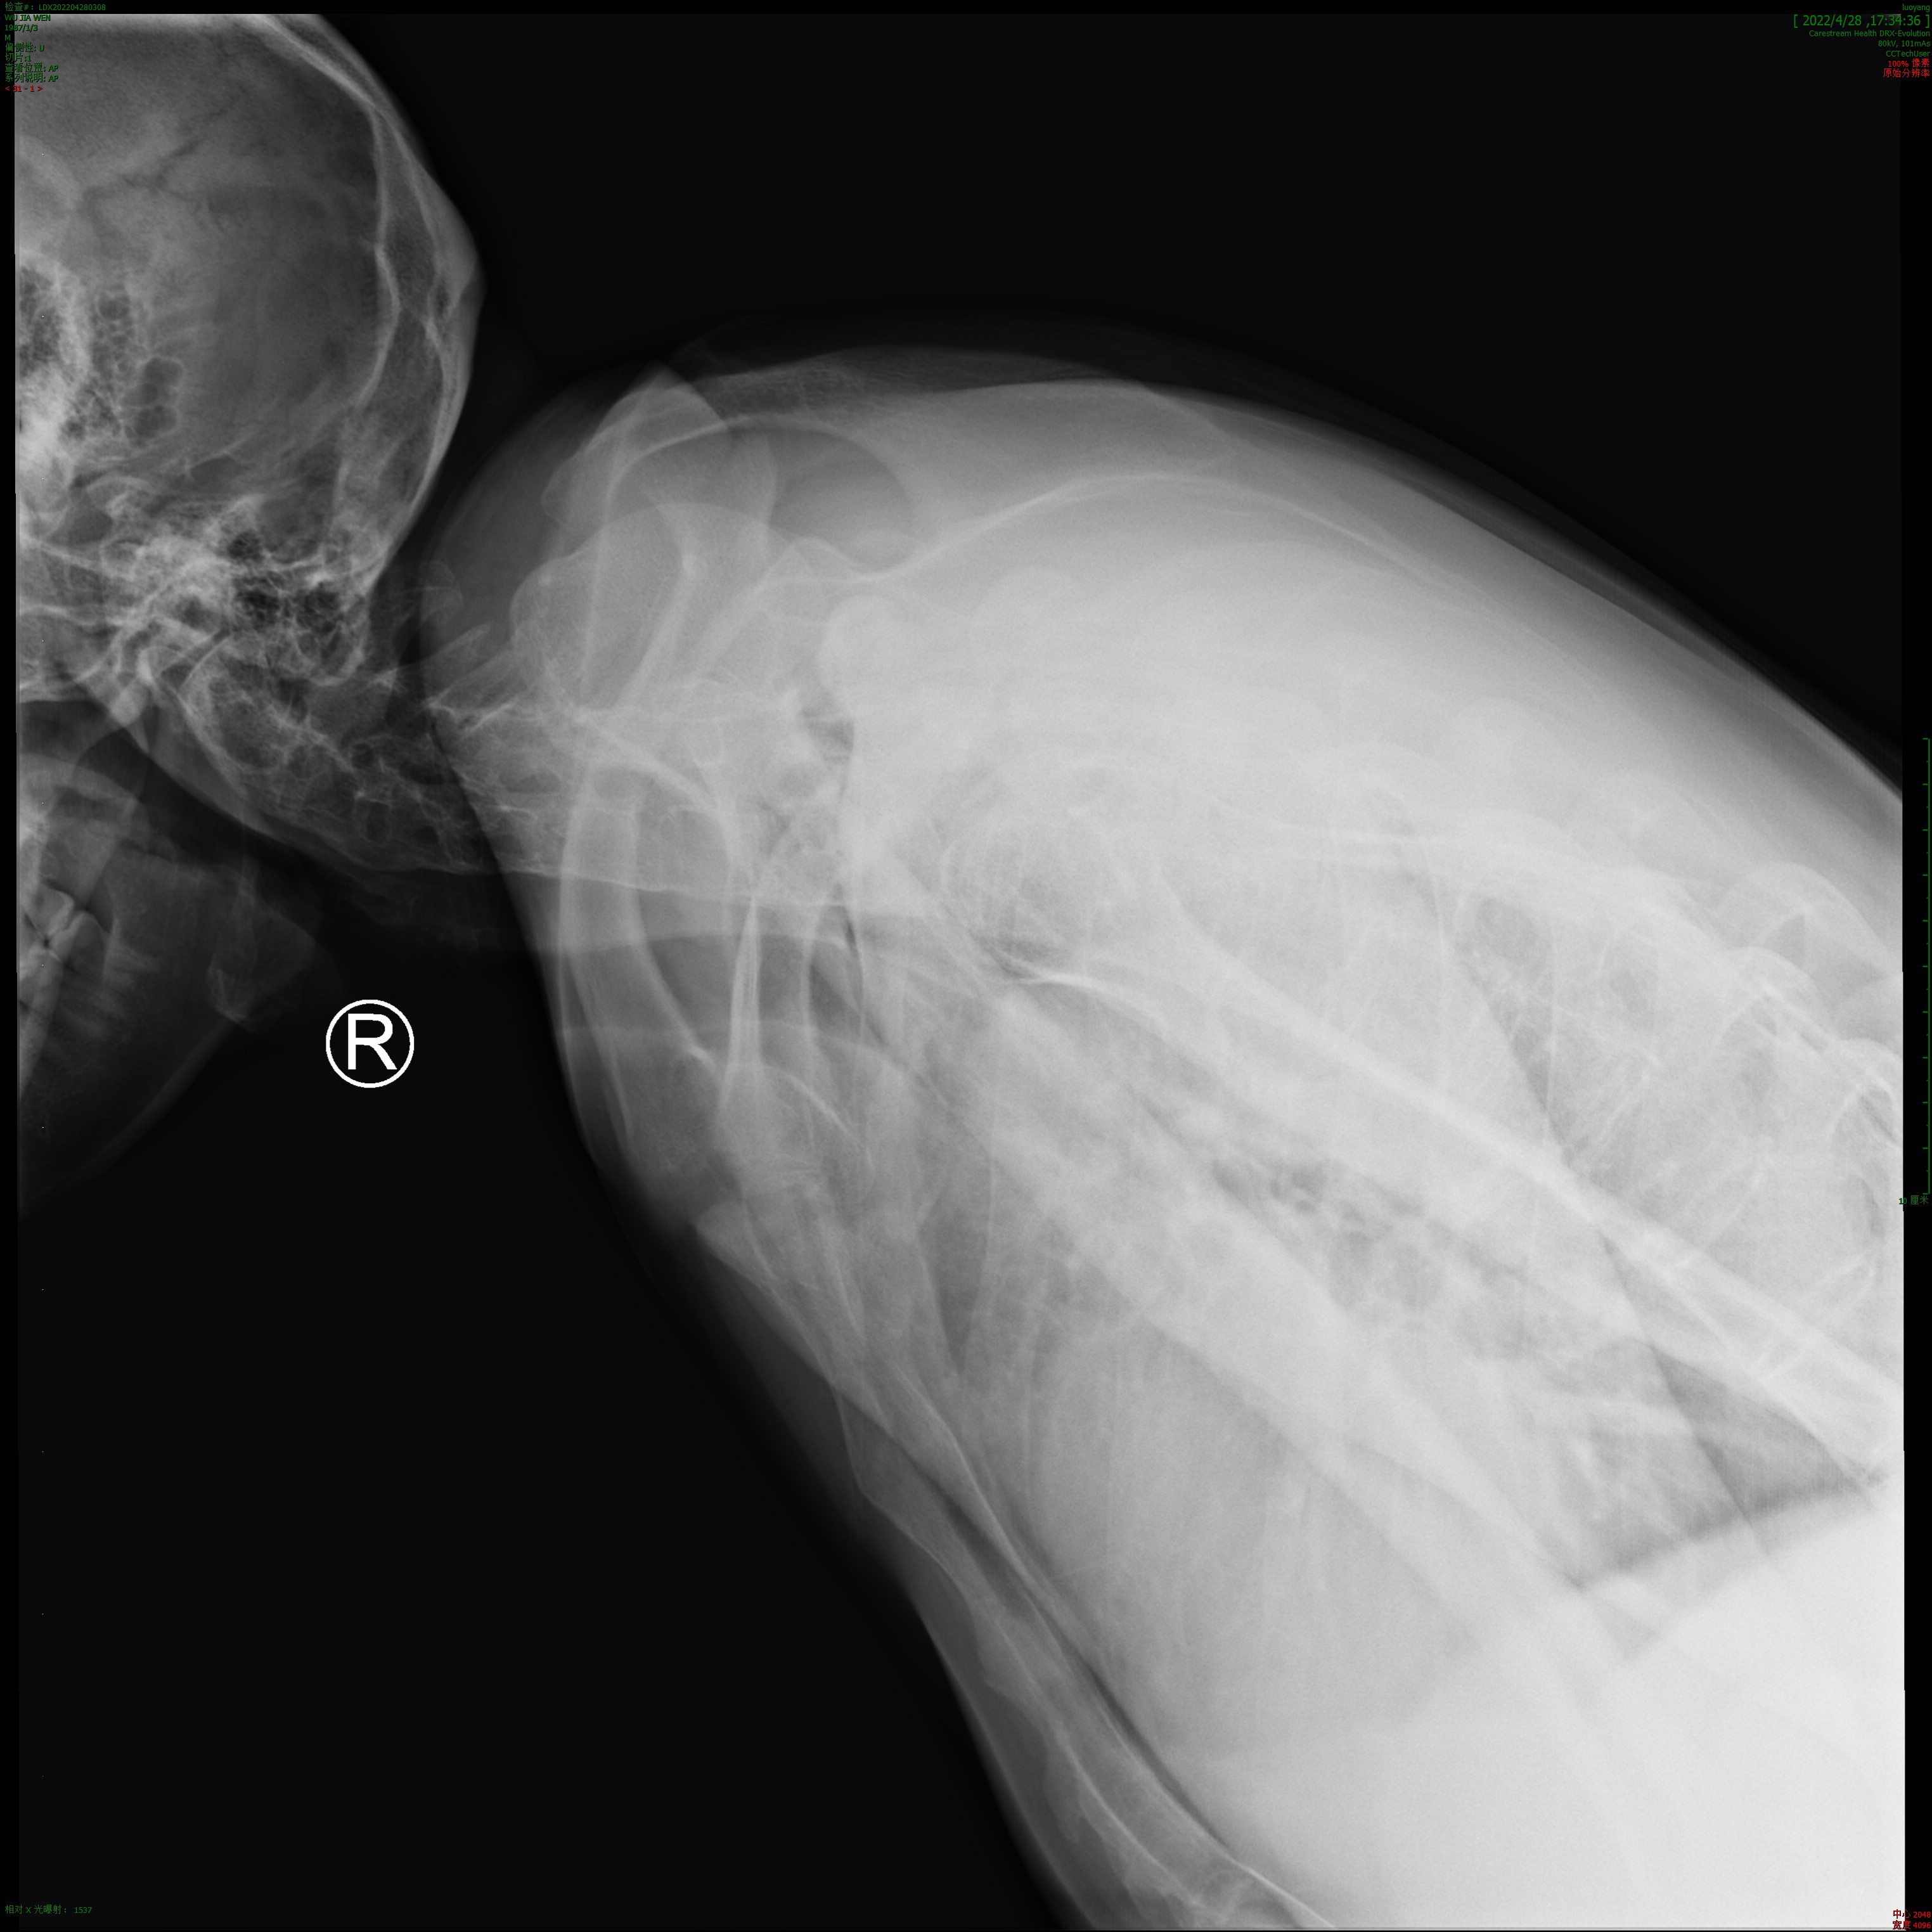

术前脊柱、髋关节影像

手术前(上)、后(下)对比